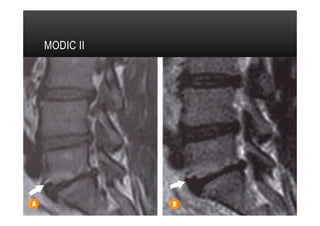

•  Tipo II

•  Alterações caracterizadas por aumento da intensidade do sinal em imagens ponderadas

em T1 e sinal isointenso ou aumentado em imagens ponderadas em T2.

•  Indicam substituição da medula óssea normal por gordura.

•  Tipo mais comum

•  Geralmente estável em 1 a 2 anos, podendendo não evoluir para tipo III

MODIC II

PLATÔS VERTEBRAIS •  TipoII •  Alterações caracterizadas por aumento da intensidade do sinal em imagens ponderadas em T1 e sinal isointenso ou aumentado em imagens ponderadas em T2. •  Indicam substituição da medula óssea normal por gordura. •  Tipo mais comum •  Geralmente estável em 1 a 2 anos, podendendo não evoluir para tipo III